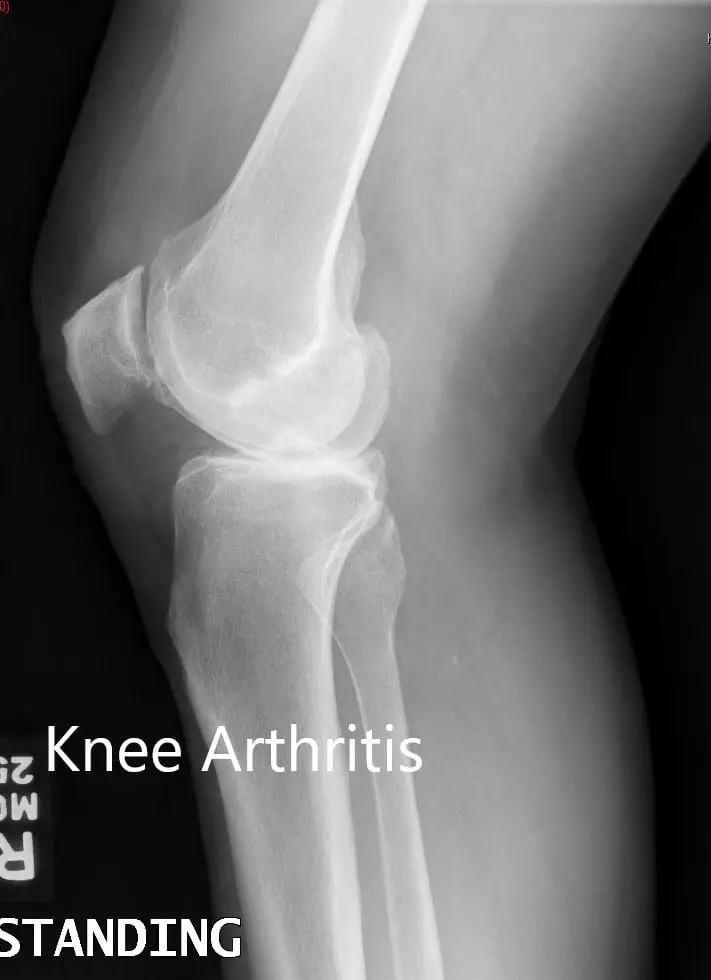

Her imaging studies of both the knee revealed severe tricompartmental osteoarthritis. Considering her lifestyle limiting knee pain, she was advised bilateral custom total knee replacement. Risks, benefits, and alternatives were discussed with the patient at length. She agreed to go ahead with a bilateral custom knee replacement.

Preoperative X-ray showing the lateral views of the right and the left knee respectively

Preoperative X-ray showing the lateral views of the right and the left knee respectively - img 2

Preoperative X-ray showing the lateral views of the right and the left knee respectively.Complete Orthopedics patient specific surgical plan for a Bilateral Customized Total Knee Replacement in a 72-year-old patient with Arthritis